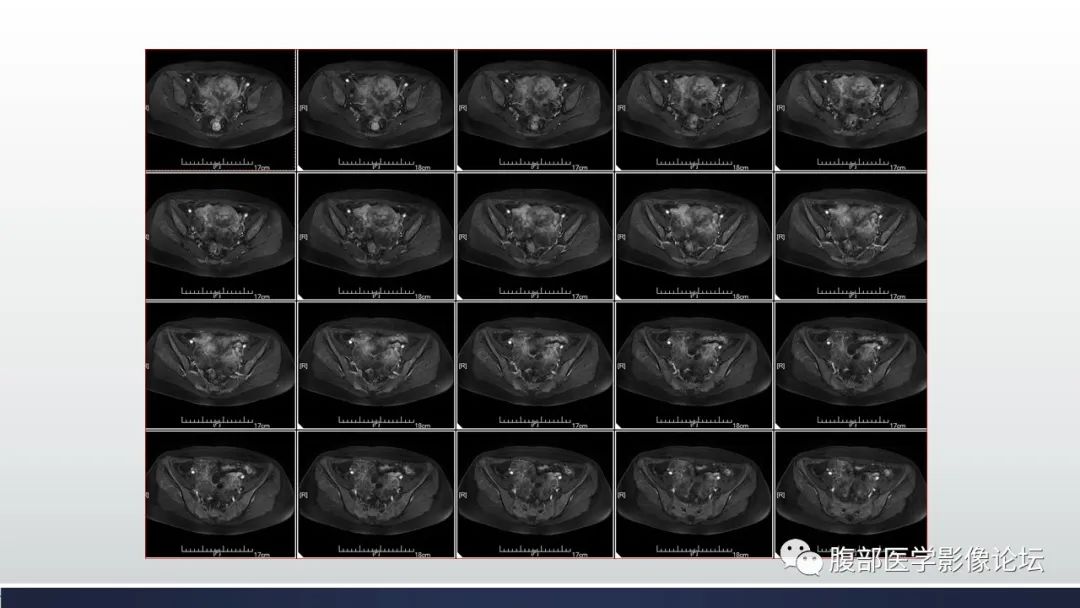

【病例】子宫内膜透明细胞癌1例MR-9

【病例】子宫内膜透明细胞癌1例MR-10

【病例】子宫内膜透明细胞癌1例MR-11

【病例】子宫内膜透明细胞癌1例MR-12